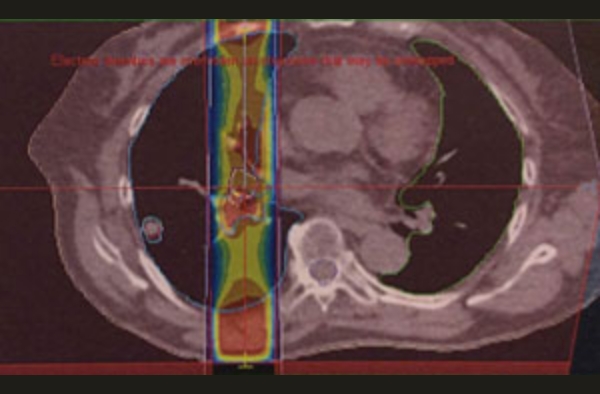

小肺がんの照射

肺がん+リンパ節

はじめのうちは、広く照射。その後、縮小照射正常肺にできるだけ当たらないように3個に分けて照射